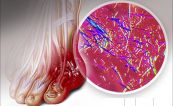

Có nhiều nguyên nhân gây tăng axit uric máu. Đối với nhóm nguyên nhân tăng axit uric máu mãn tính hay bệnh gút, có những thuốc đặc trị giúp thải axit uric và duy trì tình trạng cân bằng, hạn chế cơn đau khớp do gút cấp. Còn các nguyên nhân gây tăng axit uric thứ phát khác, điều trị giảm axit uric là điều trị nguyên nhân gây bệnh, các phương thuốc làm giảm axit uric chỉ là điều trị hỗ trợ. Cùng eLib.VN tìm hiểu bài viết dưới đây để hiểu rõ hơn về bệnh lý này nhé!